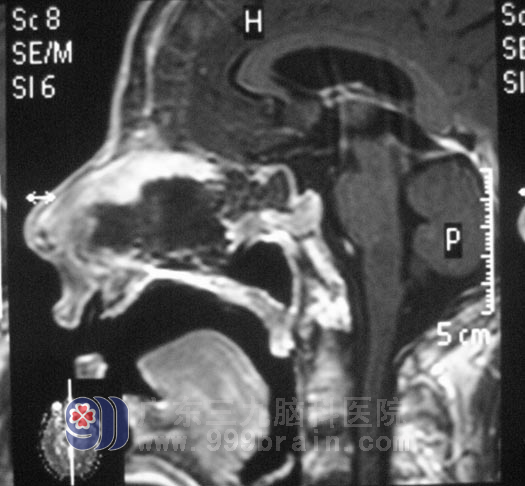

9月下旬,邱先生入住广东三九脑科医院垂体瘤诊疗中心,头颅MR检查提示占位大小约为2.5cm×3.0cm×3.3cm。考虑到邱先生的甲亢病史,在严密监测其基础代谢率及内分泌的改变都正常后,邱先生在全麻下行经鼻蝶鞍区肿瘤切除术,右侧鼻孔入路,导航定位,暴露蝶窦后见肿瘤呈灰白色,质软,血供一般,在显微镜下予肿瘤切除,术中未损伤到垂体,术后未出现脑脊液漏、尿崩等并发症,经过一周的治疗,邱先生康复出院。术后病理结果为:(鞍区)垂体腺瘤,FSH(+)。

▲手术后MR